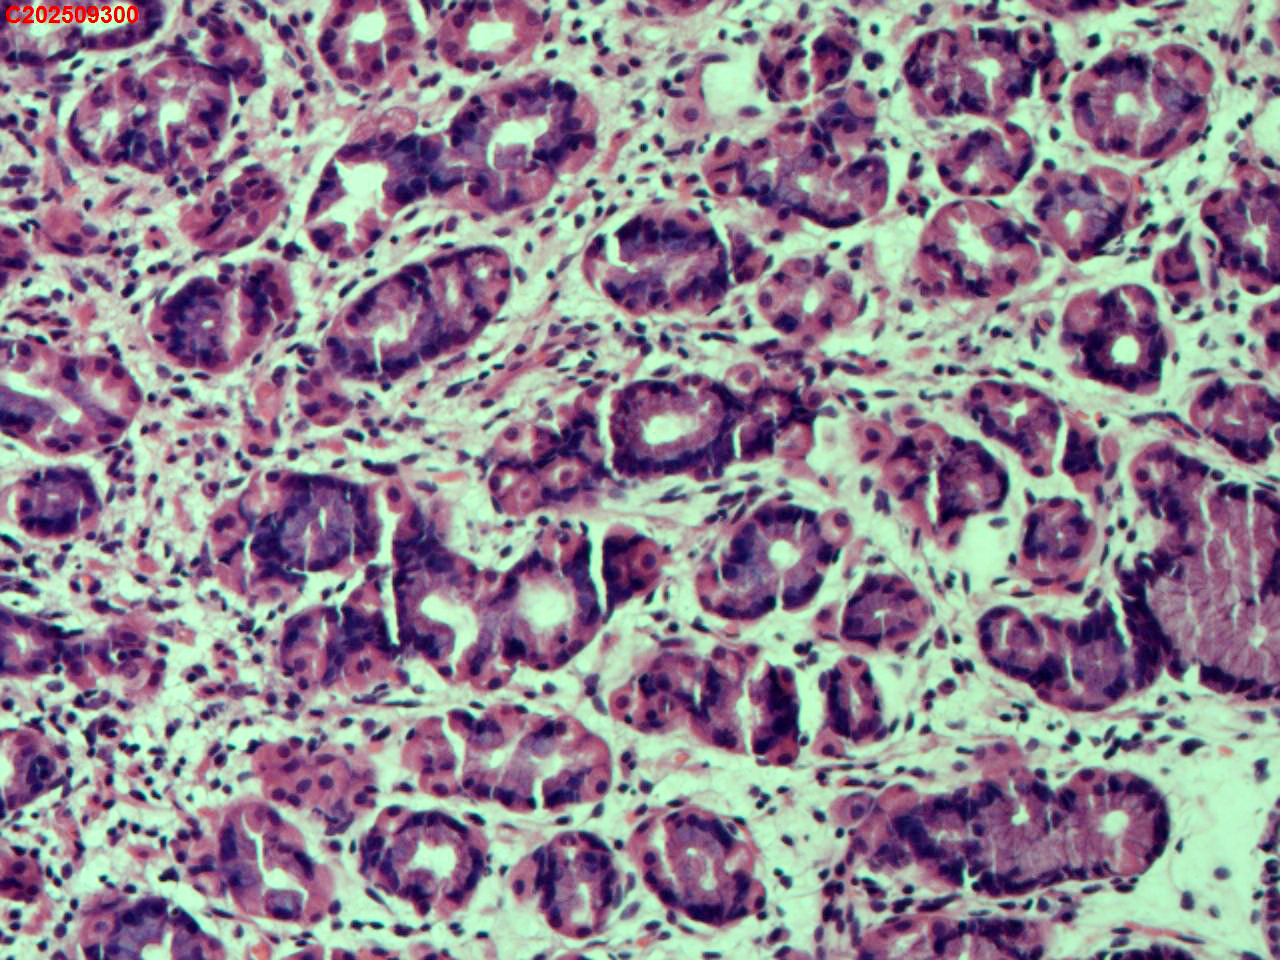

胃底粘膜

性别

女

年龄

44岁

临床诊断

胃息肉

一般病史

体检

标本名称

大体所见

胃底:可见一枚直径约2mm的半球形息肉。

增生性息肉